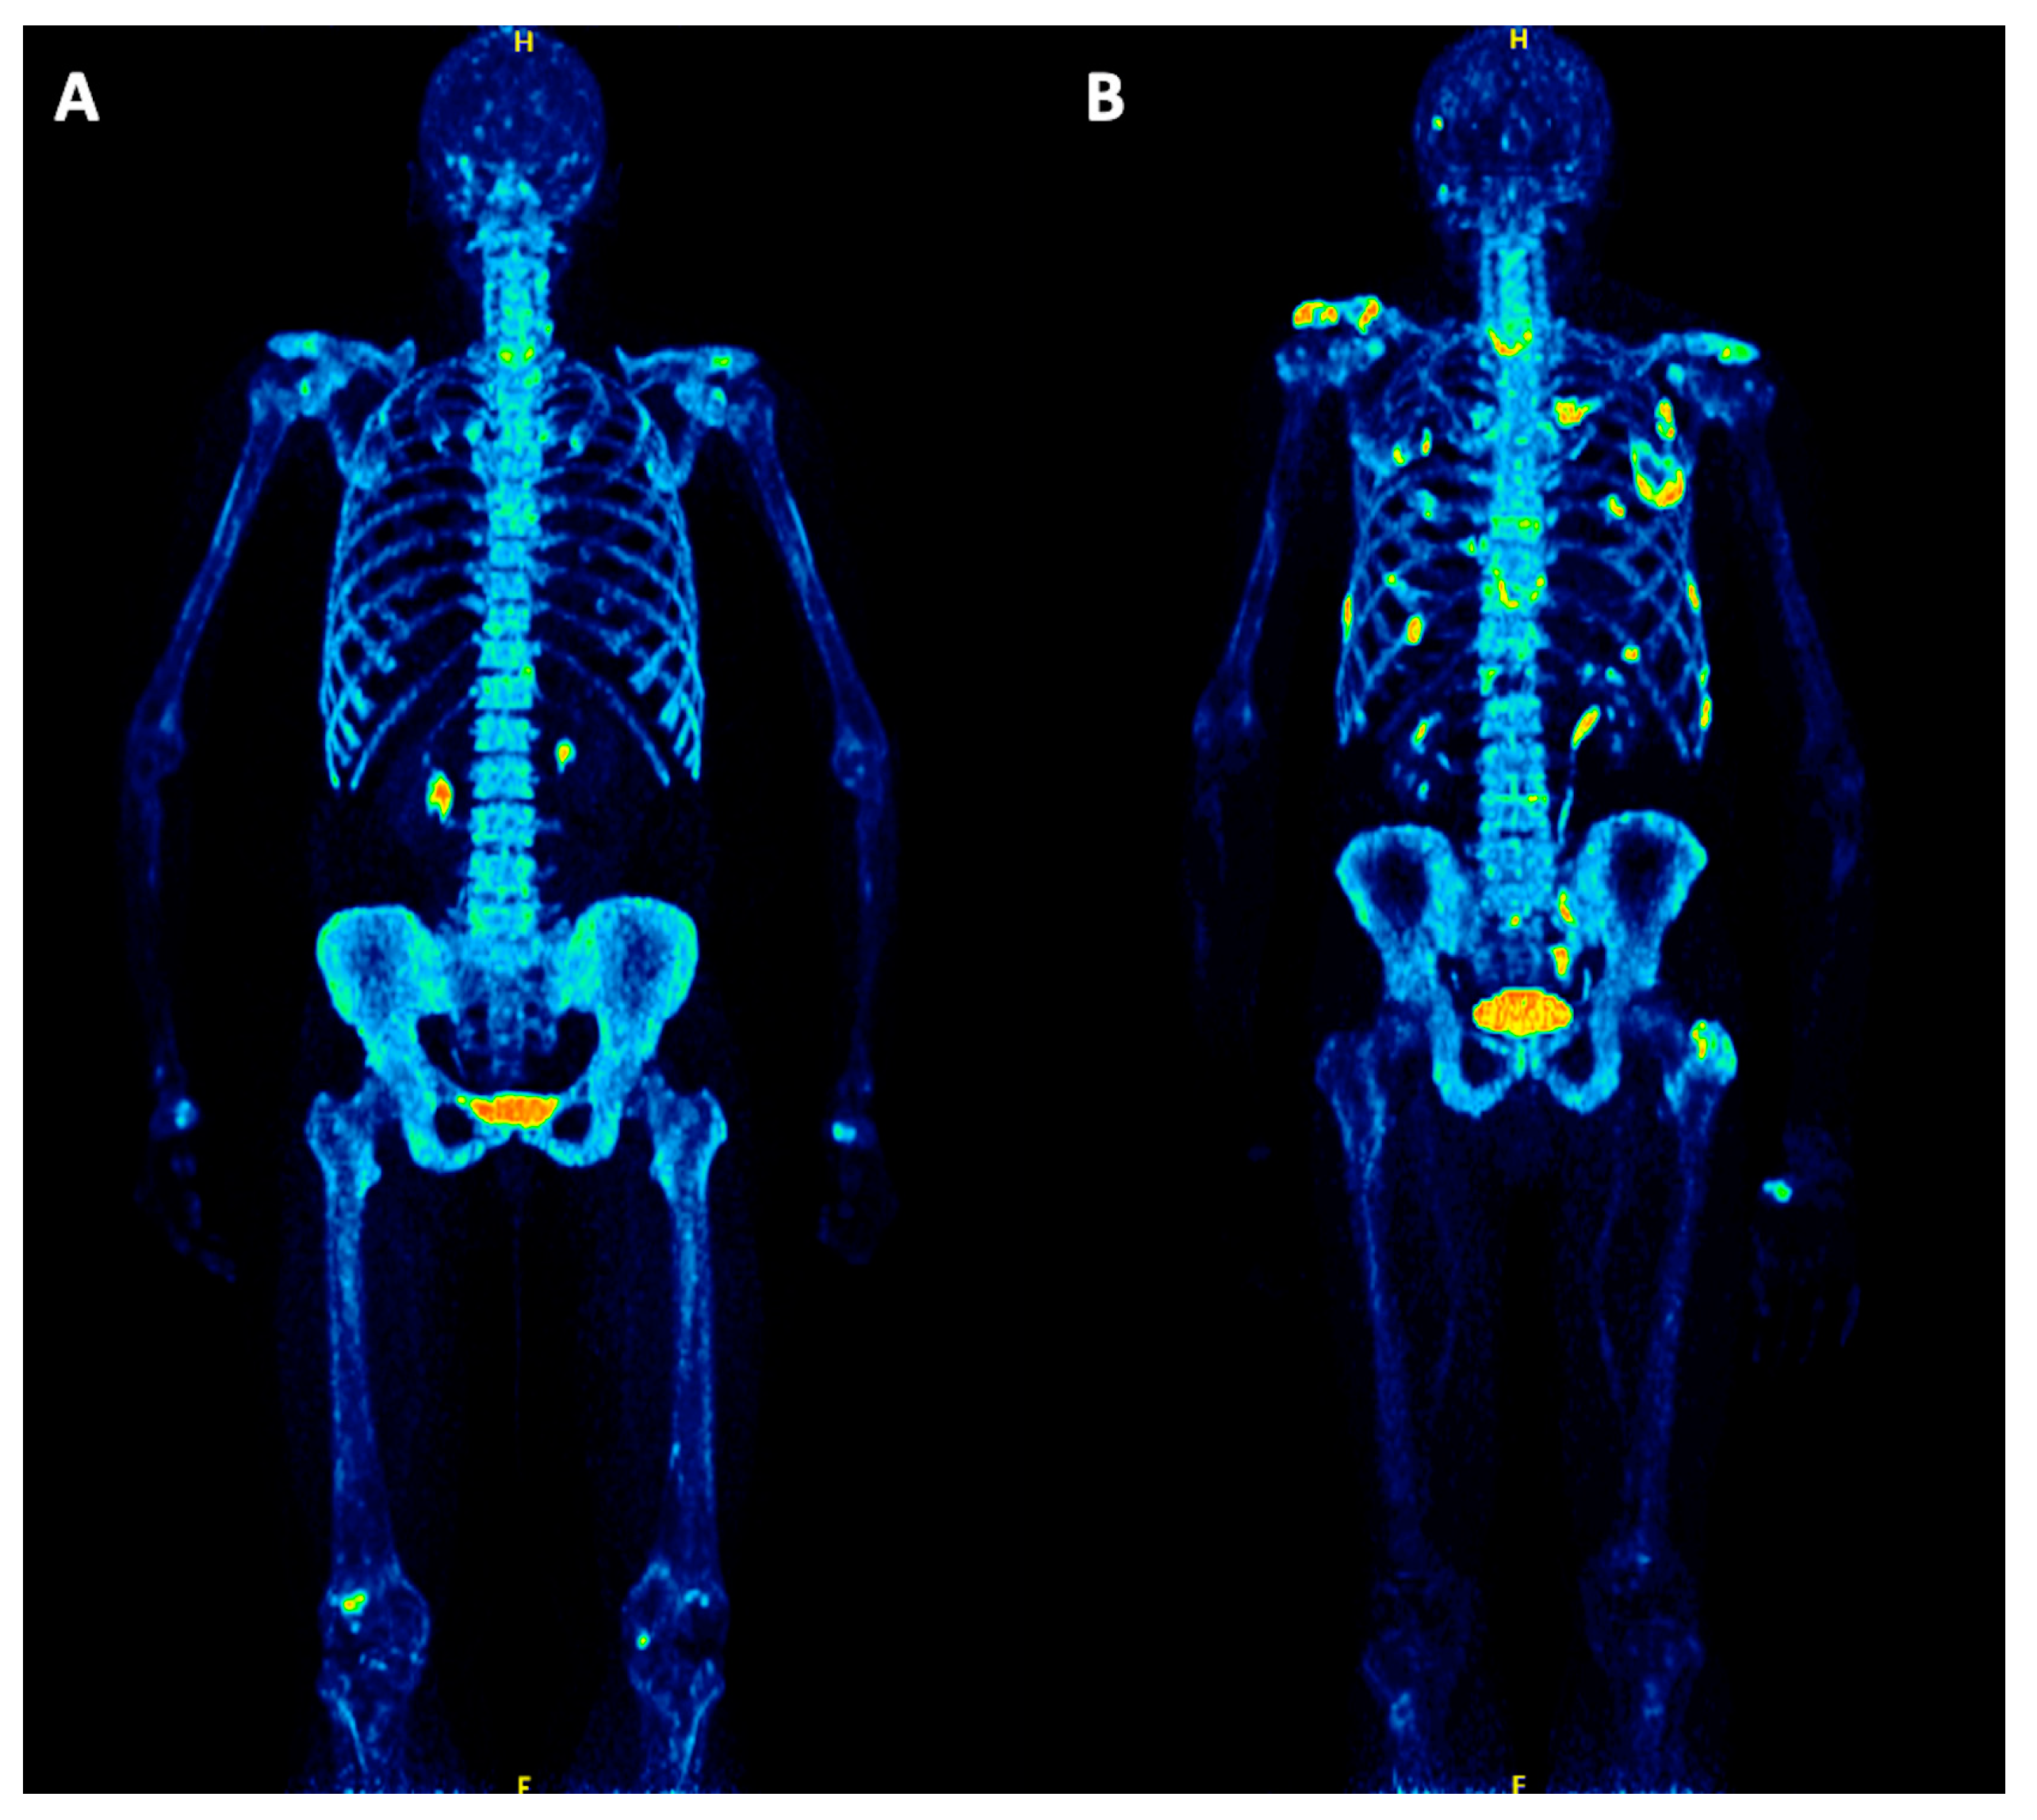

The bone scan the premisethe bone scan is the most sensitive studyfor the detection of bone disease which may be.

The pet scan uses a mildly radioactive drug to show up areas of your body where cells are more active than normal. A pet scan is typically an outpatient procedure. A bone scan or bone scintigraphy /sɪnˈtɪɡrəfi/ is a nuclear medicine imaging technique of the bone. It is done to see if the cancer has spread to other parts of the body, such as the lymph nodes, liver, lung, or bones.